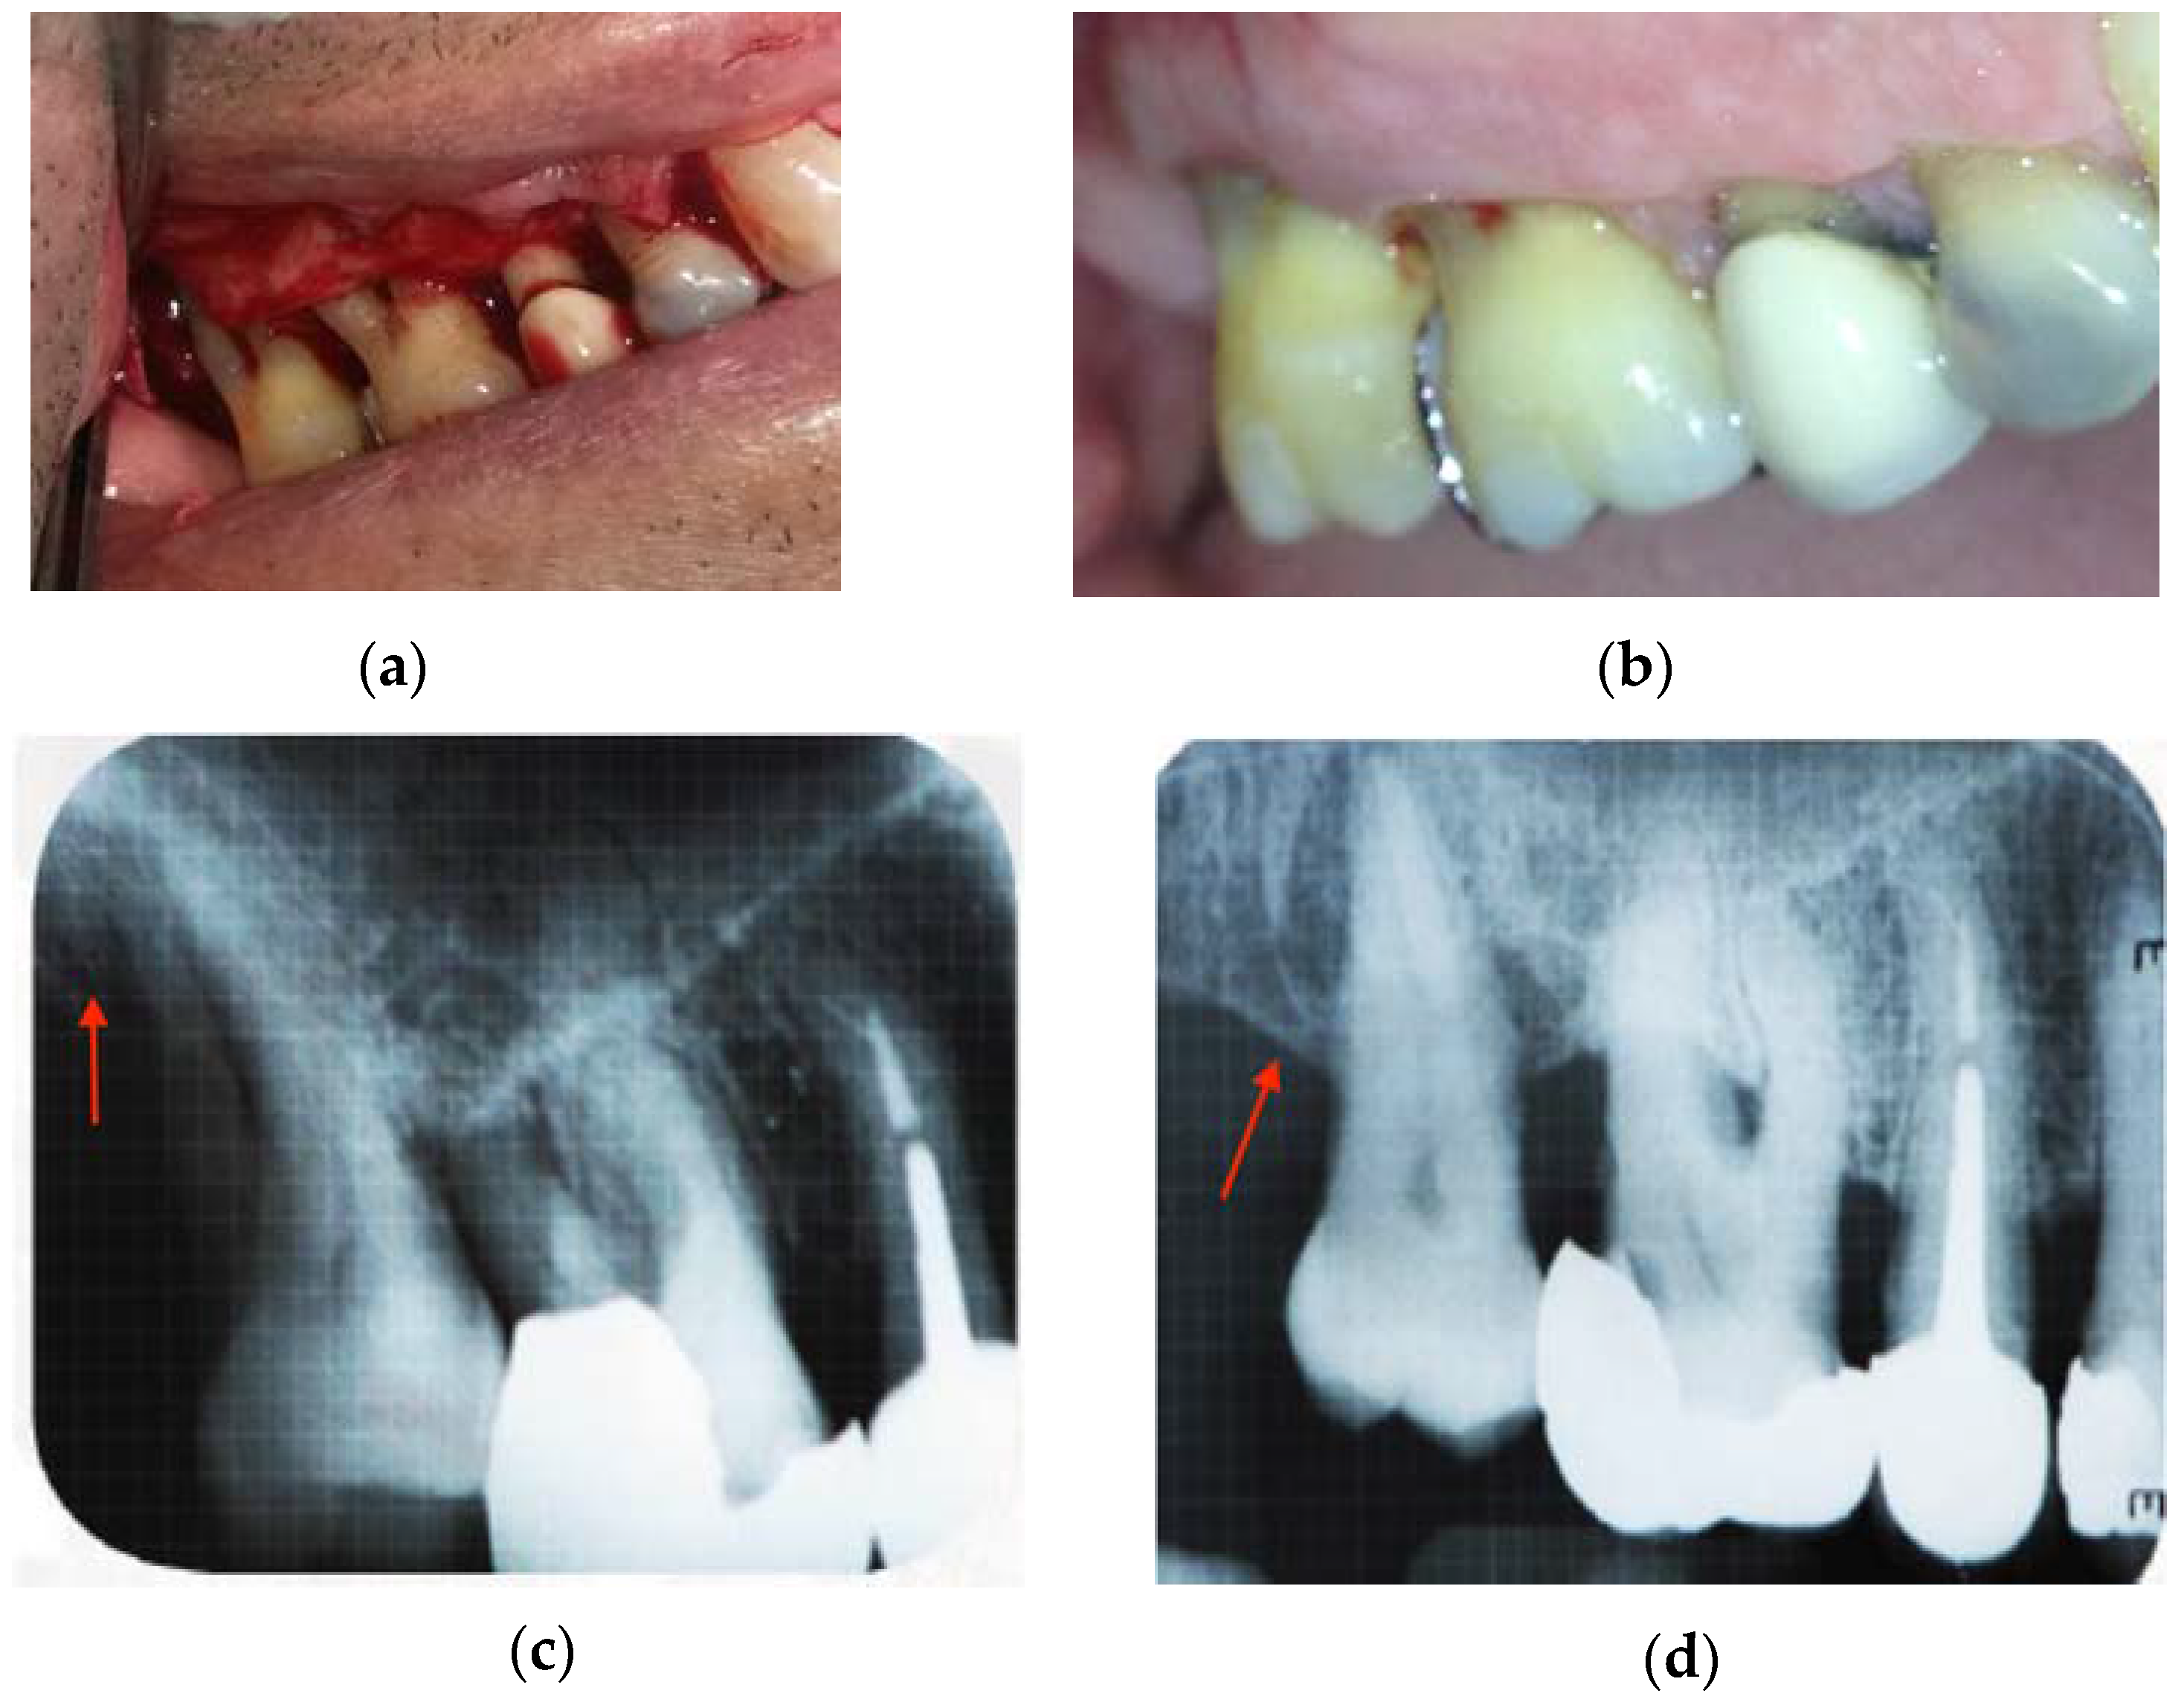

Pilot Study Using a Chitosan-Hydroxyapatite Implant for Guided Alveolar Bone Growth in Patients with Chronic Periodontitis

2. Results